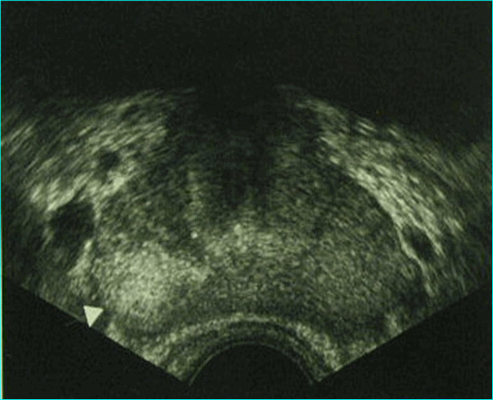

Хронический простатит (УЗИ)